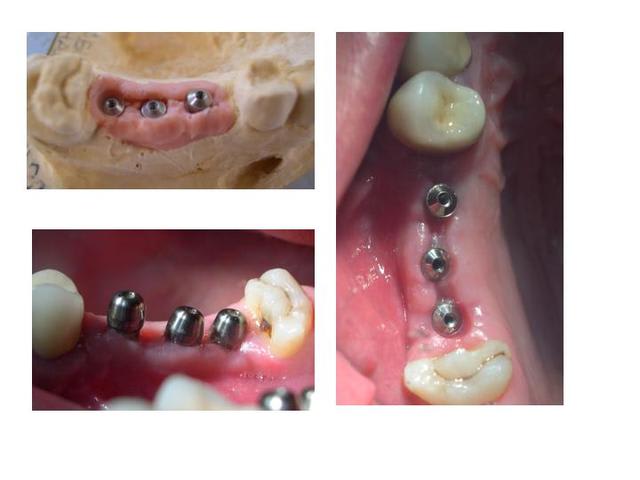

et la suite

Implants iwsvxa - Eugenol

voilà, dans un droit de suite, la réalisation prothétique provisoire sur le cas présenté.